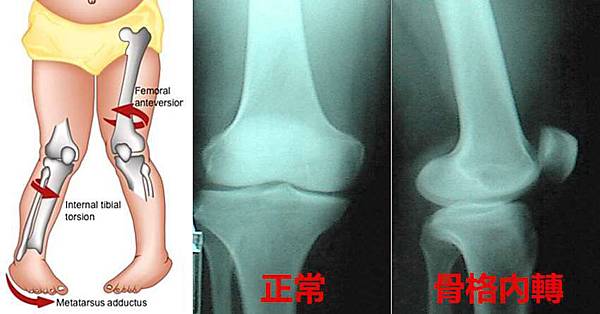

寶寶W型坐姿 當心出現下肢3大危機

孩子在5歲前,在地面上遊戲的時間較長;而且從1到2歲至進入幼稚園時期,是孩子發育的黃金時期。

爸媽及老師們要多留心小朋友的姿勢發展,並提醒孩子減少W型的坐姿及挺肚子的站姿,才不會傷脊椎與骨骼,間接影響動作協調的發展。…

更糟的是 另外一份報告表示對於發育遲緩是有影響的